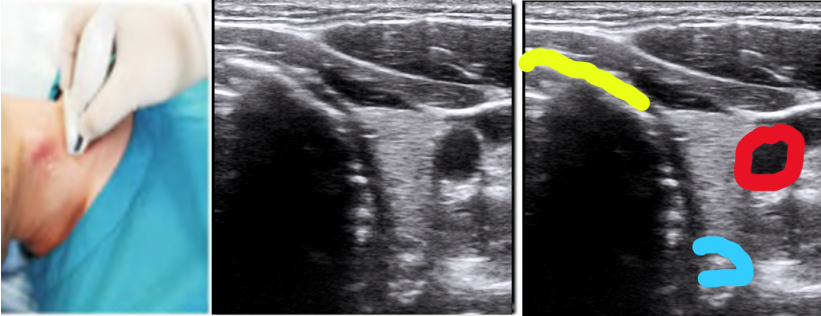

5. 超声引导下经皮气管切开术、超声引导下环甲膜穿刺

超声在气道管理中也可以用于经皮气管的切开和环甲膜的穿刺。经皮气管切开的位置在气管环,环甲膜穿刺的位置在环甲膜。相关文献报道,仅依靠体表标志和触摸确定环甲膜的成功率为30%,通过超声的颈前正中切部横断面“TACA”策略可以快速协助确定环甲膜。先找到特征性的倒V型结构的甲状软骨,然后探头轻轻往下找到空气黏膜界面(A)的环甲膜,再往下可以看到低回声的马鞍状环状软骨(C),然后再放回确定环甲膜(A)。

与环甲膜定位类似,患者取仰卧位,操作者站于患者的右侧。选择高频线阵探头横向置于颈部上方的胸骨上切迹,从中线位置观察气道。将探头水平移向患者的右侧,使探头右边界为气管的中线,然后将探头右端保持在气管中线,探头向左旋转为气管中线纵向扫描的矢状面,可以看到环状软骨的尾部。探头逐渐向头侧移动,可以看见环状软骨变大且较气管环更加靠前。此时可以将一支探针从探头底下经过作为标记,下压针干产生声影作为标记,观察穿刺路径有无明显血管和重要脏器。

图片